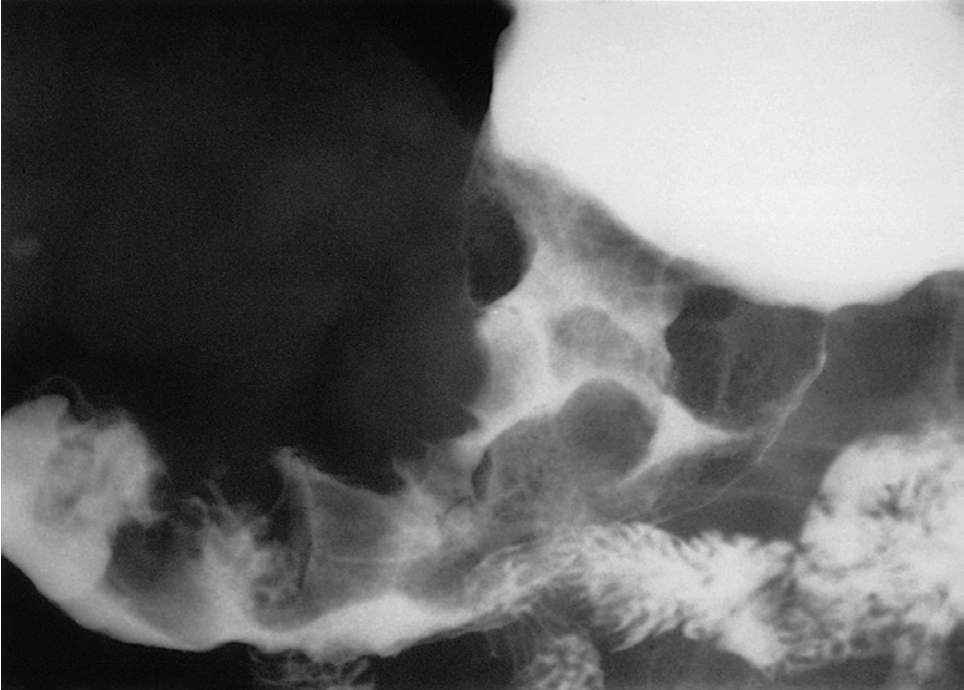

At barium examination, gastric carcinoma typically produces an irregular filling defect with alteration of the normal mucosal pattern , Computed tomography is the main imaging modality for the preoperative staging of patients with gastric cancer

Gastric carcinoma on barium study. There are a number of large filling defects in the antrum and body of the stomach.